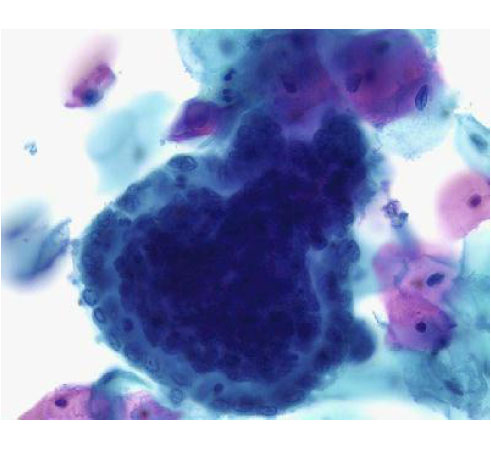

B31-7:心包积液B细胞淋巴瘤

B31-8:心包积液B细胞淋巴瘤

B31-9:心包积液B细胞淋巴瘤